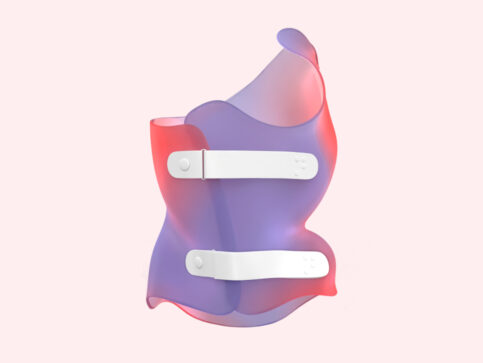

حمالة الصدر مع حزام اعوجاج العمود الفقري: 5 نصائح لضمان راحة وفعالية تصل إلى% 95 يعاني العديد من المراهقات من اعوجاج العمود الفقري (Scoliosis)، ويُعد الحزام الطبي الكامل الوقت مثل حزام PioBrace أحد أهم

كيف يذهب الطفل إلى الحمام أثناء ارتداء حزام اعوجاج العمود الفقري؟ يُعد حزام اعوجاج العمود الفقري من أهم وسائل العلاج غير الجراحي للأطفال والمراهقين المصابين بالجنف (اعوجاج العمود الفقري). ويهدف الحزام إلى تقليل الانحناء

الآثار الجانبية لحزام اعوجاج العمود الفقري: الأعراض الشائعة وكيفية التعامل معها يُعد حزام اعوجاج العمود الفقري من أكثر وسائل العلاج غير الجراحي استخدامًا لعلاج الجنف عند الأطفال والمراهقين، خاصة خلال فترة النمو. وغالبًا ما

حزام اعوجاج العمود الفقري :احتياطات أساسية يومية أثناء الأستخدام لنتائج مؤكدة تصل إلى 95% يُعد حزام اعوجاج العمود الفقري من أهم وسائل العلاج غير الجراحي للأطفال والمراهقين المصابين باعوجاج العمود الفقري. ويهدف الحزام إلى

حزام اعوجاج العمود الفقري ثلاثي الأبعاد: كيف يصحح الانحناء بنتائج مثبتة تصل إلى 85٪ يُعد اعوجاج العمود الفقري من الحالات الشائعة التي قد تظهر عند الأطفال والمراهقين خلال فترة النمو. وغالبًا ما يلاحظ الأهل

تصميم حزام اعوجاج العمود الفقري: كيف يؤثر الشكل الجمالي على تقبّل المريض والالتزام بالعلاج؟ يعاني العديد من الأطفال والمراهقين من اعوجاج العمود الفقري، وهي حالة تظهر غالبًا خلال فترة النمو السريع في سن المراهقة.